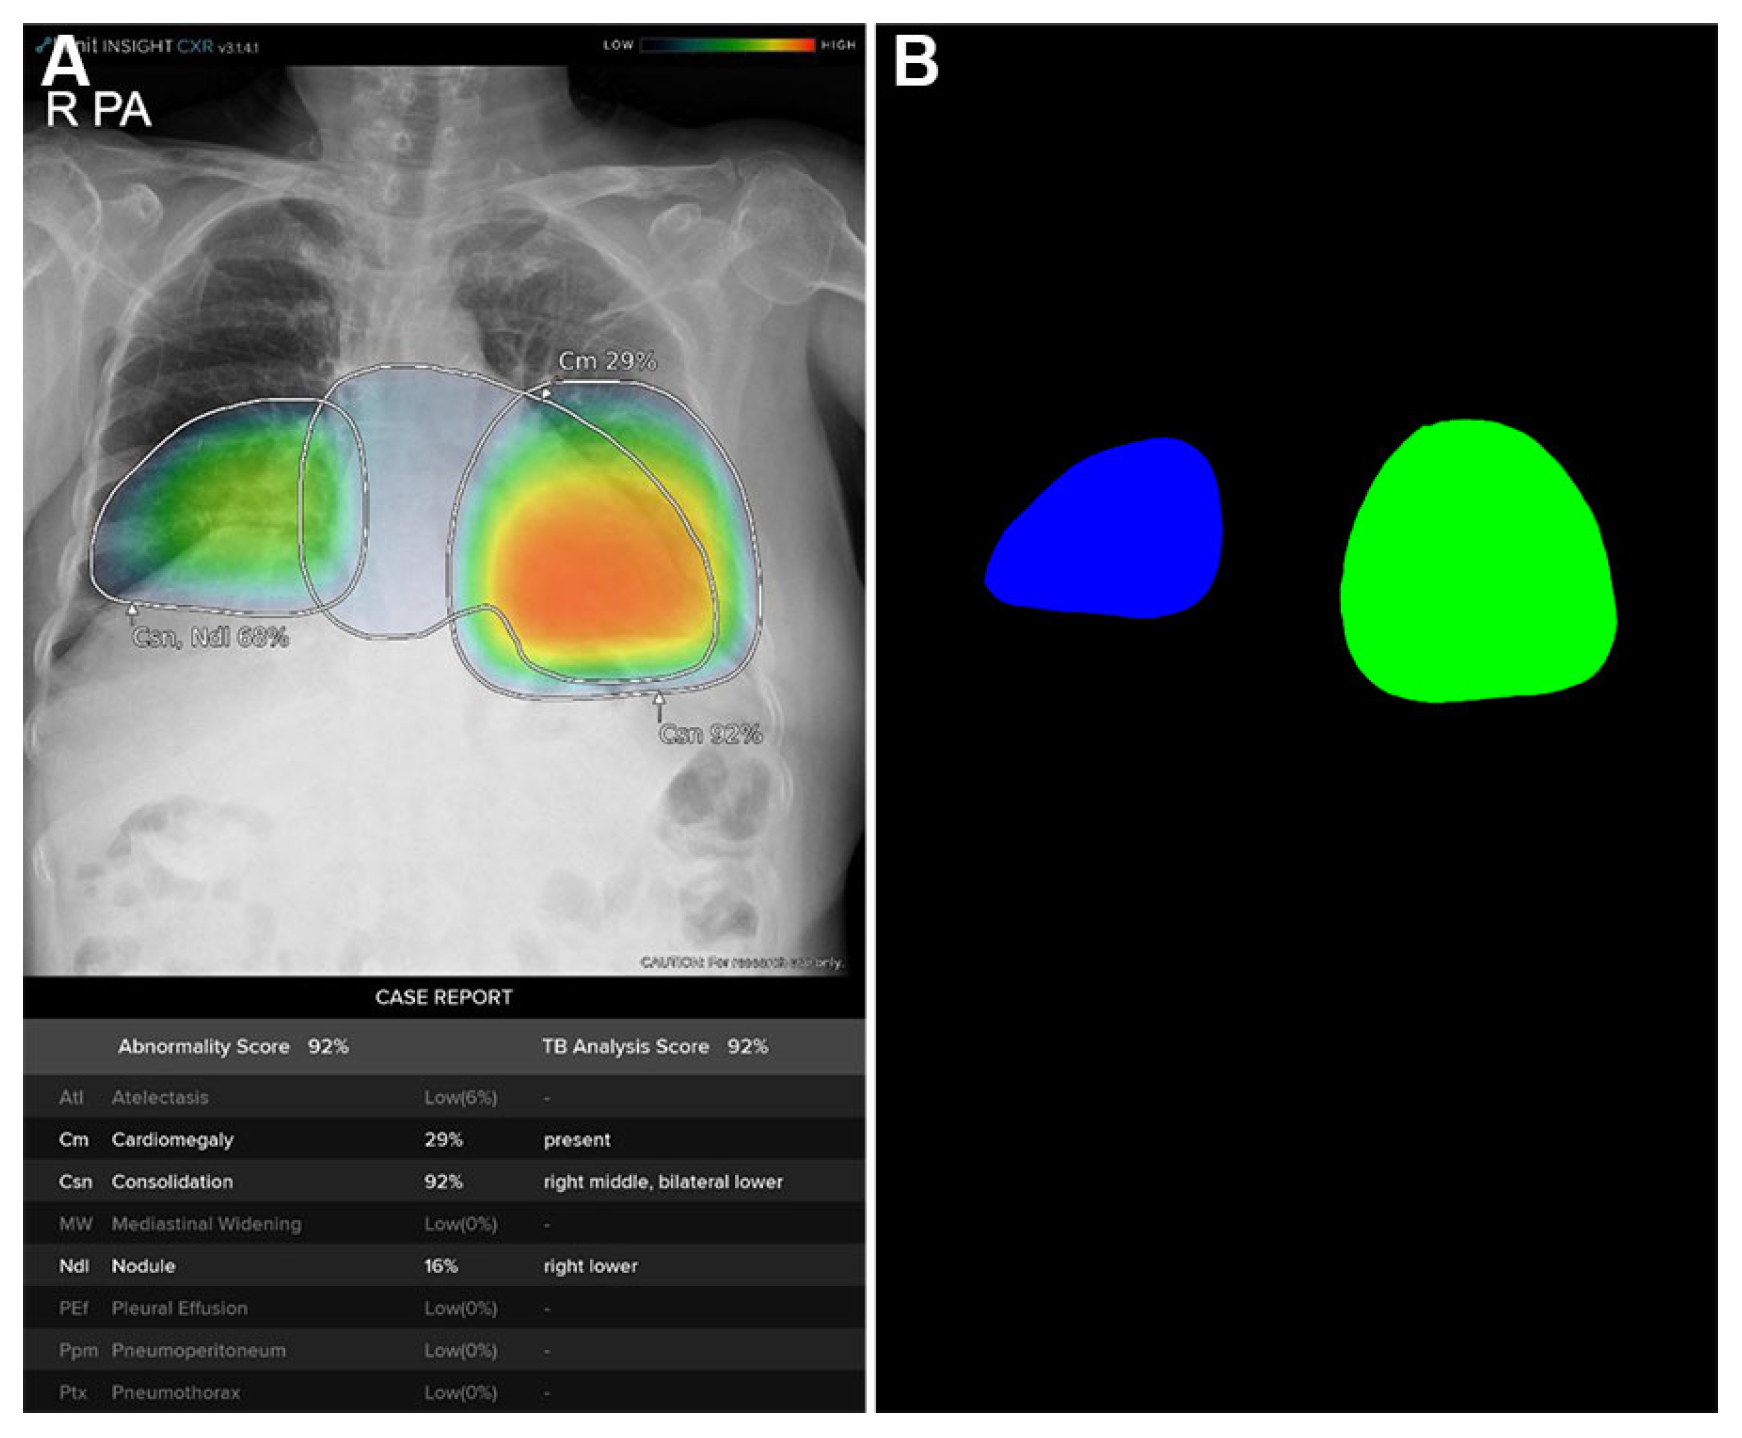

The quantitative image analysis pipeline is illustrated in Figure 2. The DLAD system analyzed CXRs with a median interval of 3.57 days (range: 1.73–5.56) between serial examinations. Using consolidation probability scores and Grad-CAM-based localization maps (Figure 3A), regions of interest (ROIs) were quantified through heatmap area segmentation using OpenCV Python program version 4.2.0 (Figure 3B). Segmentation quality was visually confirmed by a board-certified radiologist (BLINDED). The ‘area’ represented the fractional percentage of total ROI sizes relative to the entire CXR. We defined ‘probability’ as the maximum consolidation probability score among all ROIs. The ‘weighted area’ was calculated using the following equation:

Figure 3. Quantitative areas of consolidation automatically calculated from the deep learning-based automatic detection algorithm (DLAD) localization map using OpenCV python program. (A) Localization map from the chest X-ray of a 77-year-old COVID-19 patient showing bilateral consolidation with annotations and abnormality scores/probabilities suggested by DLAD. (B) OpenCV program automatically detects and calculates quantitative area of each consolidation heatmap.